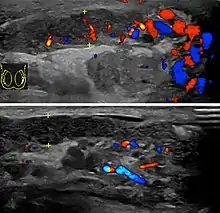

Epididymitis usually has a gradual onset. Typical findings are redness, warmth and swelling of the scrotum, with tenderness behind the testicle, away from the middle (this is the normal position of the epididymis relative to the testicle). The cremasteric reflex (elevation of the testicle in response to stroking the upper inner thigh) remains normal.[1] This is a useful sign to distinguish it from testicular torsion. If there is pain relieved by elevation of the testicle, this is called Prehn's sign, which is, however, non-specific and is not useful for diagnosis.[13] Before the advent of sophisticated medical imaging techniques, surgical exploration was the standard of care. Today, Doppler ultrasound is a common test: it can demonstrate areas of blood flow and can distinguish clearly between epididymitis and torsion. However, as torsion and other sources of testicular pain can often be determined by palpation alone, some studies have suggested that the only real benefit of an ultrasound is to assure the person that they do not have testicular cancer.[14]: p.237 Nuclear testicular blood flow testing is rarely used.